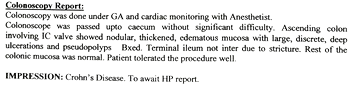

COLONOSCOPY

Colonoscopy is a procedure where the doctor can examine the lowermost part of the digestive tract

by a flexible instrument called as Colonoscope. Common indications for Colonoscopy are

7. Frank blood in the stool, occult blood in the stool or anaemia.

These conditions are seen more often in elderly people where Colonoscopy is essential for making an early diagnosis of cancer of the colon.

The correct diagnosis of cancer of the colon or rectum if made in time can offer a curative treatment.

Altered bowel habits, watery or semisolid stools, gripping pain in abdomen, mucus and blood in the stool,

incomplete evacuation can all be due to a condition called as colitis. Colitis has got different causes

like ulcerative colitis, Crohn’s disease, infections, tuberculosis, amoebic colitis, bacillary dysentery and many more.

Corrcet diagnosis by Colonoscopy will allow patients to be treated properly.